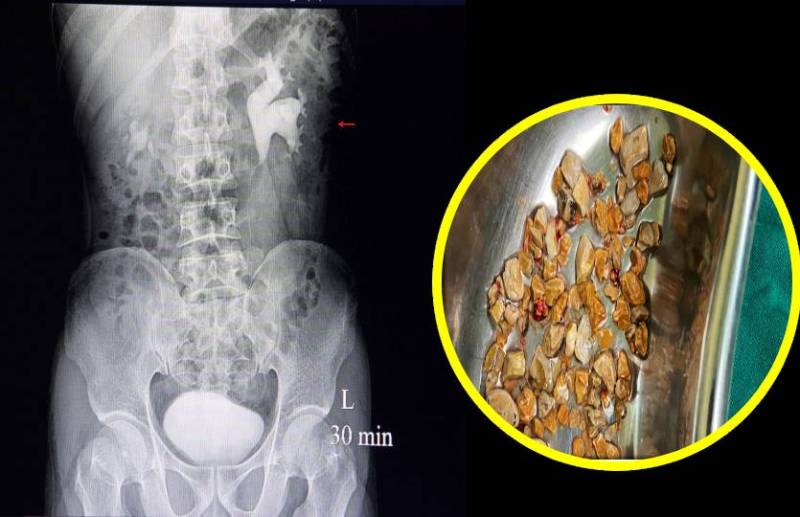

शरीर में गुर्दे की पथरी तब बनती है जब नमक और खनिज क्रिस्टलीकृत होकर यूरिनरी सिस्टम में कहीं भी एक साथ चिपक जाते हैं। इसे यूरोलिथियासिस या कैल्सी के रूप में भी जाना जाता है। इसके होने पर लोगों के मन में सबसे पहले ऑपरेशन करवाने का ख्याल आता है लेकिन आप चाहें तो घरेलू उपायों से भी इसको हटा सकते हैं। जानिए कौन से हैं वे उपाय...